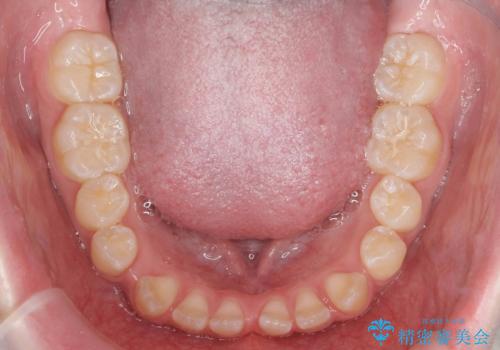

- 前歯の隙間を主訴に来院。

顎の大きさに比べて歯が小さく、隙間が目立っていました。

マウスピース矯正で隙間を閉じる処置を行いました。